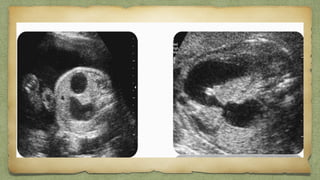

Double bubble sign

๏ฑ Another bubble adjacent to stomach bubble

Other than GB

Esophageal AtresiaEsophageal Atresia

๏ฑ 2nd

bubble equal or smaller than stomach bubble

๏ฑ Shows communication with stomach

D/Dโ€ฆDuodenal atresia

Choledochal cyct

Duplication cyst